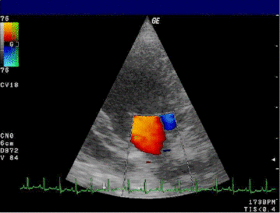

Doppler echocardiography is a procedure that uses ultrasound technology to examine the heart or blood vessels.[1] An echocardiogram uses high frequency sound waves to create an image of the heart while the use of Doppler technology allows determination of the speed and direction of blood flow by utilizing the Doppler effect.

An echocardiogram can, within certain limits, produce accurate assessment of the direction of blood flow and the velocity of blood and cardiac tissue at any arbitrary point using the Doppler effect. One of the limitations is that the ultrasound beam should be as parallel to the blood flow as possible. Velocity measurements allow assessment of cardiac valve areas and function, any abnormal communications between the left and right side of the heart, any leaking of blood through the valves (valvular regurgitation), calculation of the cardiac output and calculation of E/A ratio[2] (a measure of diastolic dysfunction). Contrast-enhanced ultrasound using gas-filled microbubble contrast media can be used to improve velocity or other flow-related medical measurements.

An advantage of Doppler echocardiography is that it can be used to measure blood flow within the heart without invasive procedures such as cardiac catheterization.